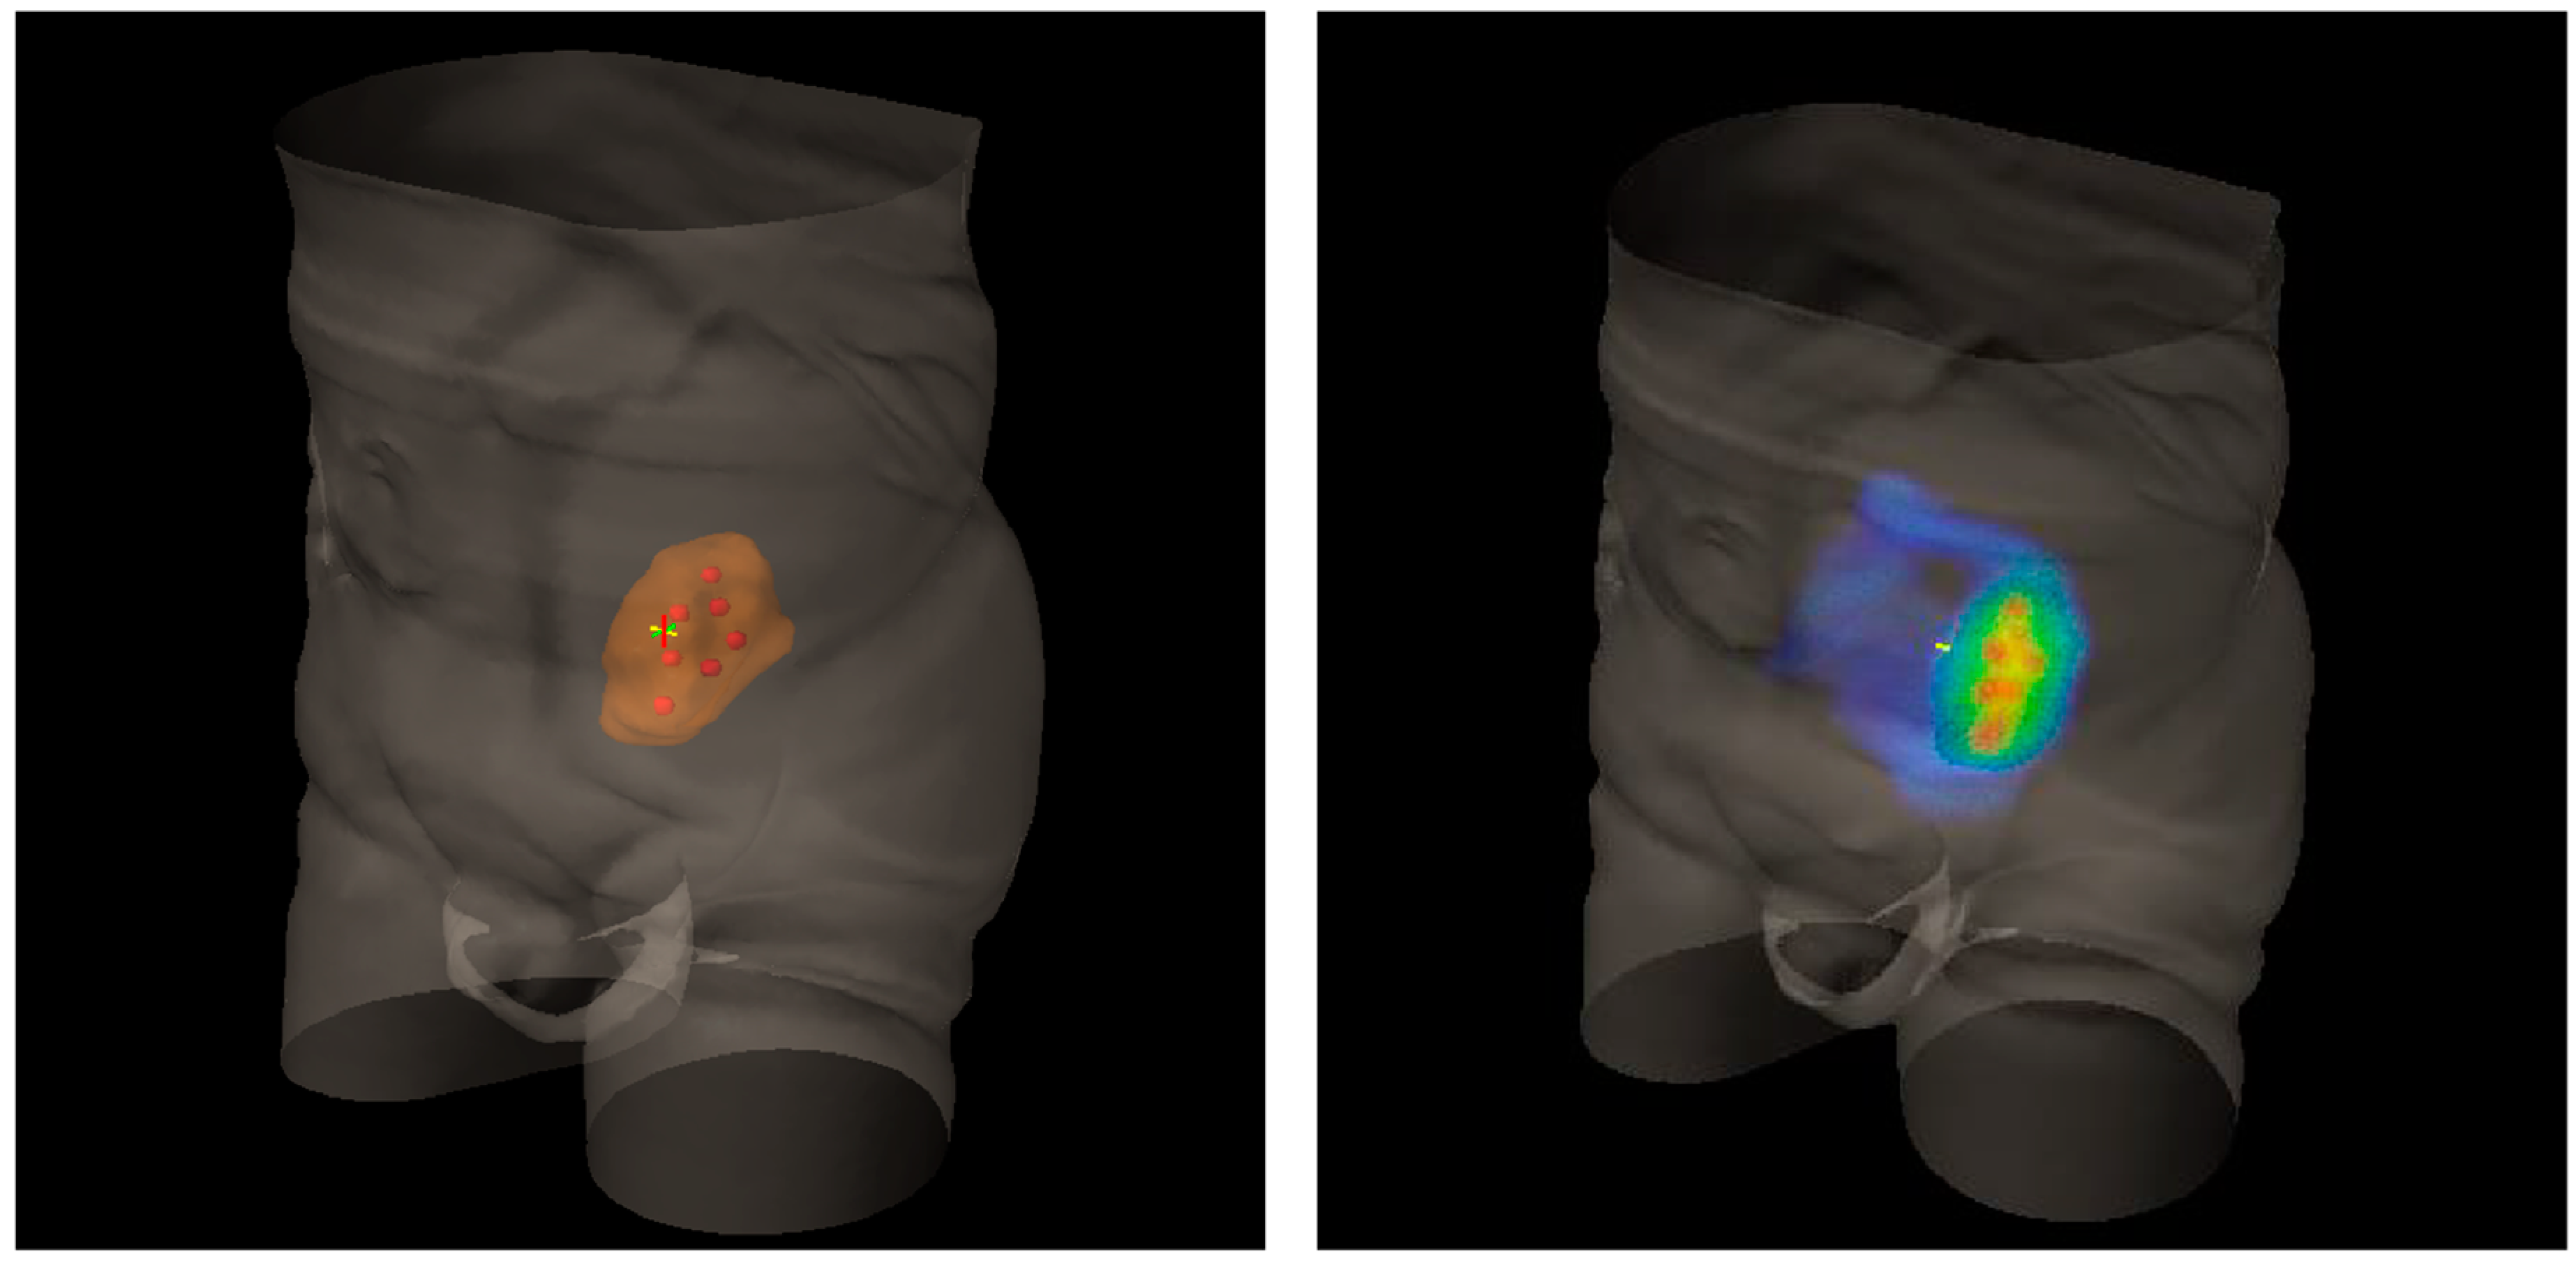

2. Lattice Radiotherapy: Concept

3. Clinical Use of LATTICE Radiotherapy

7. A Look to the Future and Open Questions

- Amendola, B.E.; Perez, N.C.; Mayr, N.A.; Wu, X.; Amendola, M. Spatially Fractionated Radiation Therapy Using Lattice Radiation in Far-advanced Bulky Cervical Cancer: A Clinical and Molecular Imaging and Outcome Study. Radiat. Res. 2020, 194, 724–736. [Google Scholar] [CrossRef]

- Asur, R.; Butterworth, K.T.; Penagaricano, J.A.; Prise, K.M.; Grifn, R.J. High dose bystander efects in spatially fractionated radia-tion therapy. Cancer Lett. 2015, 356, 52–57. [Google Scholar] [CrossRef] [Green Version]

- Yan, W.; Khan, M.K.; Wu, X.; Simone, C.B.; Fan, J.; Gressen, E.; Zhang, X.; Limoli, C.L.; Bahig, H.; Tubin, S.; et al. Spatially fractionated radiation therapy: History, present and the future. Clin. Transl. Radiat. Oncol. 2020, 20, 30–38. [Google Scholar] [CrossRef] [Green Version]

- Tubin, S.; Khan, M.K.; Salerno, G.; Mourad, W.F.; Yan, W.; Jeremic, B.; Tubin, S. Mono-institutional phase 2 study of innovative Stereotactic Body RadioTherapy targeting PArtial Tumor HYpoxic (SBRT-PATHY) clonogenic cells in unresectable bulky non-small cell lung cancer: Profound non-targeted effects by sparing peri-tumoral immune microenvironment. Radiat. Oncol. 2019, 14, 1–11. [Google Scholar] [CrossRef] [Green Version]